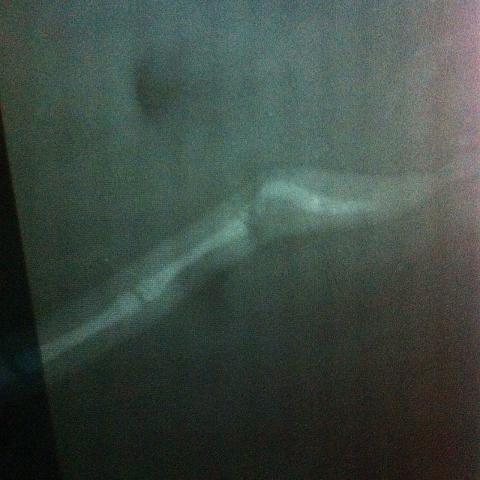

Здраствуйте ,подскажите пожалуйста у нашей собаки перелом хвоста был или врожденный загиб ? И что можно сделать ?пятна на снимке это отпечатки пальцев.